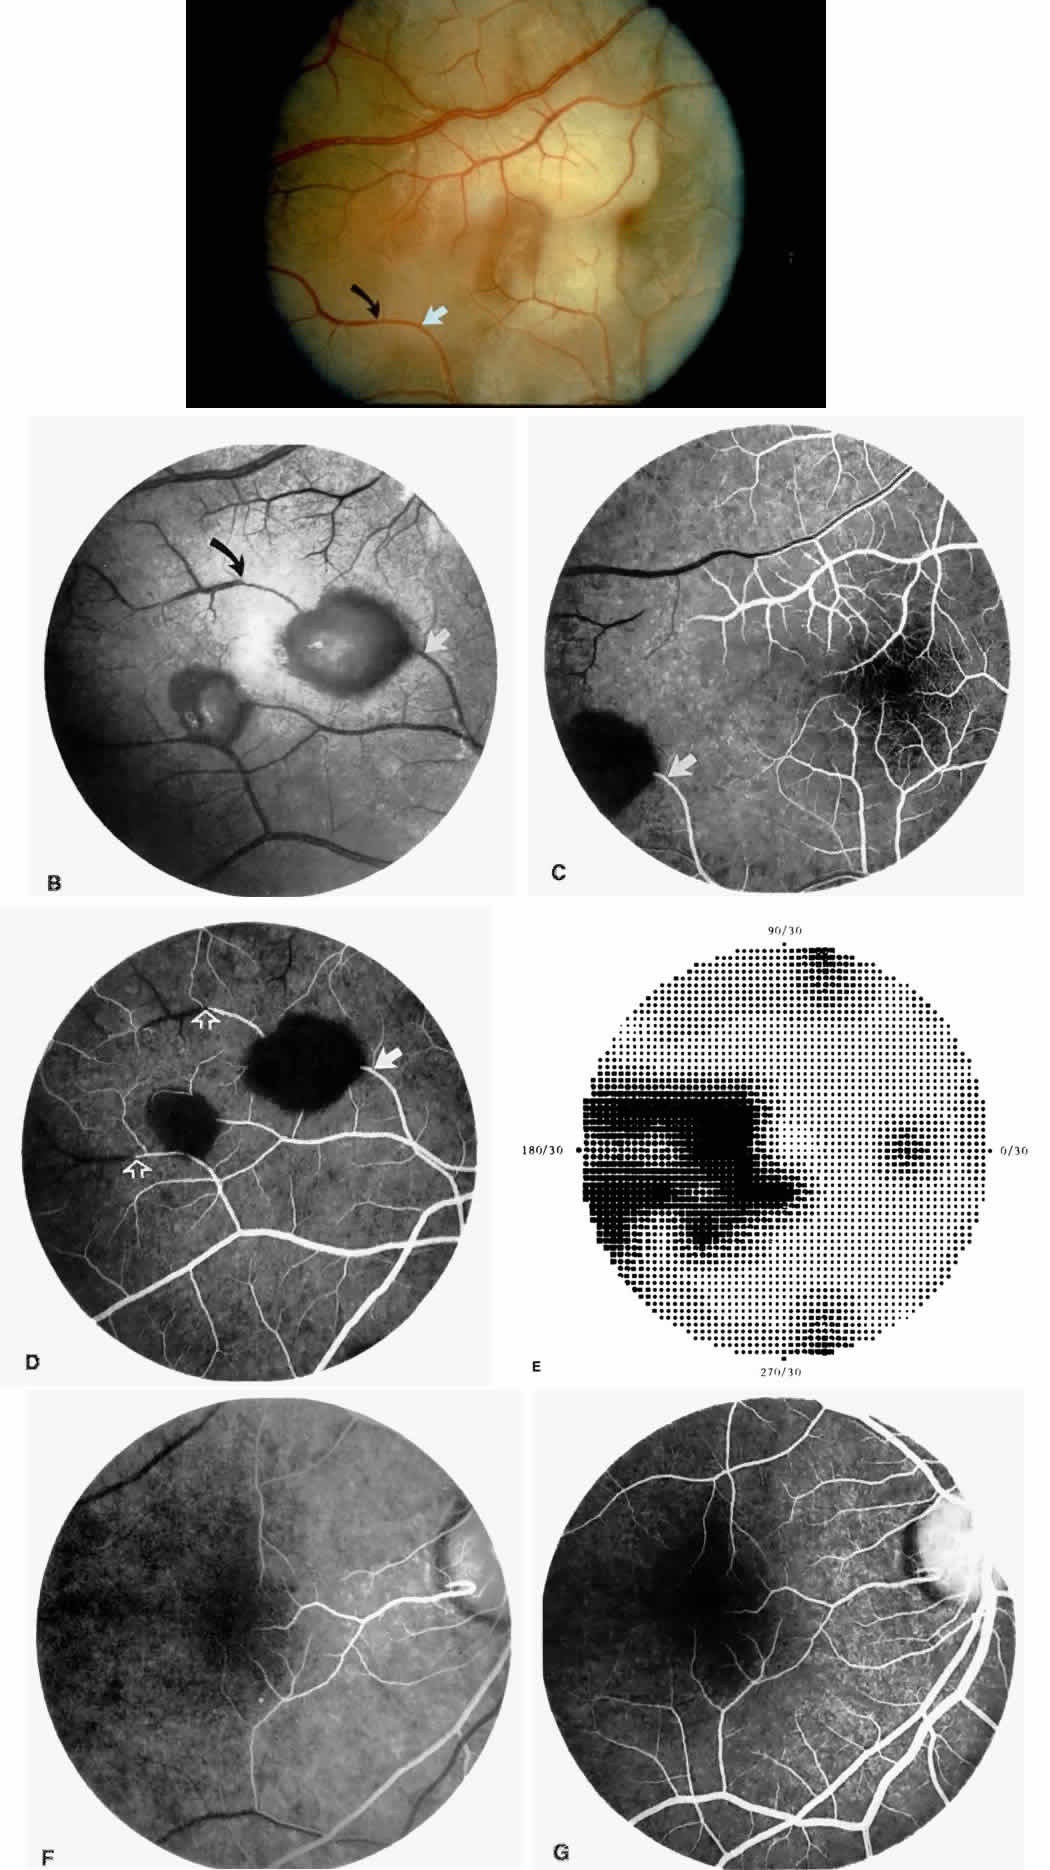

Choroidal vascular occlusions may occur focally at the level of the choroidal precapillary arteriole or capillary bed (Elschnig's spots) or from posterior ciliary artery occlusion. Although focal precapillary arteriole occlusions have not been specifically identified with sickle cell disease, clinical and histopathologic evidence of spontaneous posterior ciliary artery occlusions have been reported in sickle cell disease.109,110 The findings are similar to those described following compression of the eye during general anesthesia and after heavy peripheral photocoagulation.111,112 In the acute phase, the occlusions appear as white, circumscribed, triangular patches at the level of the retinal pigment epithelium and outer retina. Over the following weeks, the white lesions fade and retinal pigment epithelial mottling develops (Fig. 15). Since patients with acute ciliary artery occlusions may be asymptomatic and the diagnosis is often based solely on the appearance of peripheral pigment mottling, the frequency of this complication remains uncertain.

Focal areas of atrophy of the choriocapillaris have been seen histopathologically on postmortem examination of patients with homozygous sickle cell anemia. Mild sclerosis of the choriocapillaris, focal peripheral photoreceptor loss, and areas of choroidal neovascularization also have been noted.110 It has been suggested that choroidal ischemia plays a role in the development of angioid streaks in sickle cell disease. The one histopathologic report of angioid streaks indicated that the basement membrane of the underlying choriocapillaris endothelial cells was slightly thickened and that sickled erythrocytes were found within patent lumina of the choriocapillaris.77 No specific evidence exists to support a relationship between choroidal ischemia and angioid streaks.

Retinal Hemorrhages, Iridescent Spots, and Black Sunbursts

Retinal hemorrhages (“salmon patches”), found most commonly in the equatorial periphery, can be observed after an abrupt occlusion and rupture of an intermediate-sized retinal arteriole (Fig. 16).113 Because the hemorrhages typically appear adjacent or distal to an intraluminal obstruction, it is likely that ischemic necrosis causes a weakening of the vessel wall and that reperfusion of the vessel causes a rupture of the damaged vessel wall, resulting in a hemorrhage (Fig. 17).100 Acutely, these hemorrhages are bright red, but after several days, the partially degenerated blood acquires a characteristic orange-red color (hence the name salmon patch). In most cases, these hemorrhages are asymptomatic. The majority of these hemorrhages remain confined to the sensory retina; however, blood may leak through the internal limiting membrane into the vitreous or dissect deeper into the subretinal space (Fig. 18).114 Resolution occurs over days to weeks and may result in a focal area of atrophic split retina (a “schisis” cavity), a pigmented retinal scar, or a grayish-white vitreous deposit, depending on the location of the hemorrhage (Color Plate 1B through G).115 The blood is slowly cleared by macrophages.

|

Intraretinal blood breakdown products, either extracellular or within macrophages, may appear as refractile copper-colored granules (“iridescent spots”") (Color Plate 1H). Macular iridescent schisis lesions have not been described clinically, but they have been observed on histologic examination.114

The occluded vessels may reopen, and the capillary network in the area of a schisis cavity may appear normal; however, more commonly, the vessels will remain closed (Fig. 19). In rare cases, an area of retinal neovascularization may be found within a schisis cavity (Fig. 20).

|

Black pigmented spiculate or stellate chorioretinal lesions (“black sunbursts”) are typically found around or anterior to the equator and adjacent to an arteriole.70 Occasionally, a pigmented lesion may be seen trailing from an arteriole or as a cuff of pigment overlying the vessel (Color Plate 2A).83 Additionally, the overlying arteriole may be occluded. Refractile deposits are often seen interspersed with the pigment. Black sunbursts are believed to be due to deep retinal blood stimulating pigment epithelial migration, hyperplasia, and hypertrophy.116,117 Histopathologic findings support this hypothesis,114 and the development of black sunbursts has been documented in an area of previous intraretinal and subretinal hemorrhage (see Color Plate 1E, F, and G).114,115 An alternative explanation for black sunbursts is the occurrence of choroidal ischemia and aborted choroidal neovascularization.22,118 A spontaneous chorioretinal neovascular membrane was shown to occur within a black sunburst in a 14-year-old girl with homozygous sickle cell anemia.119